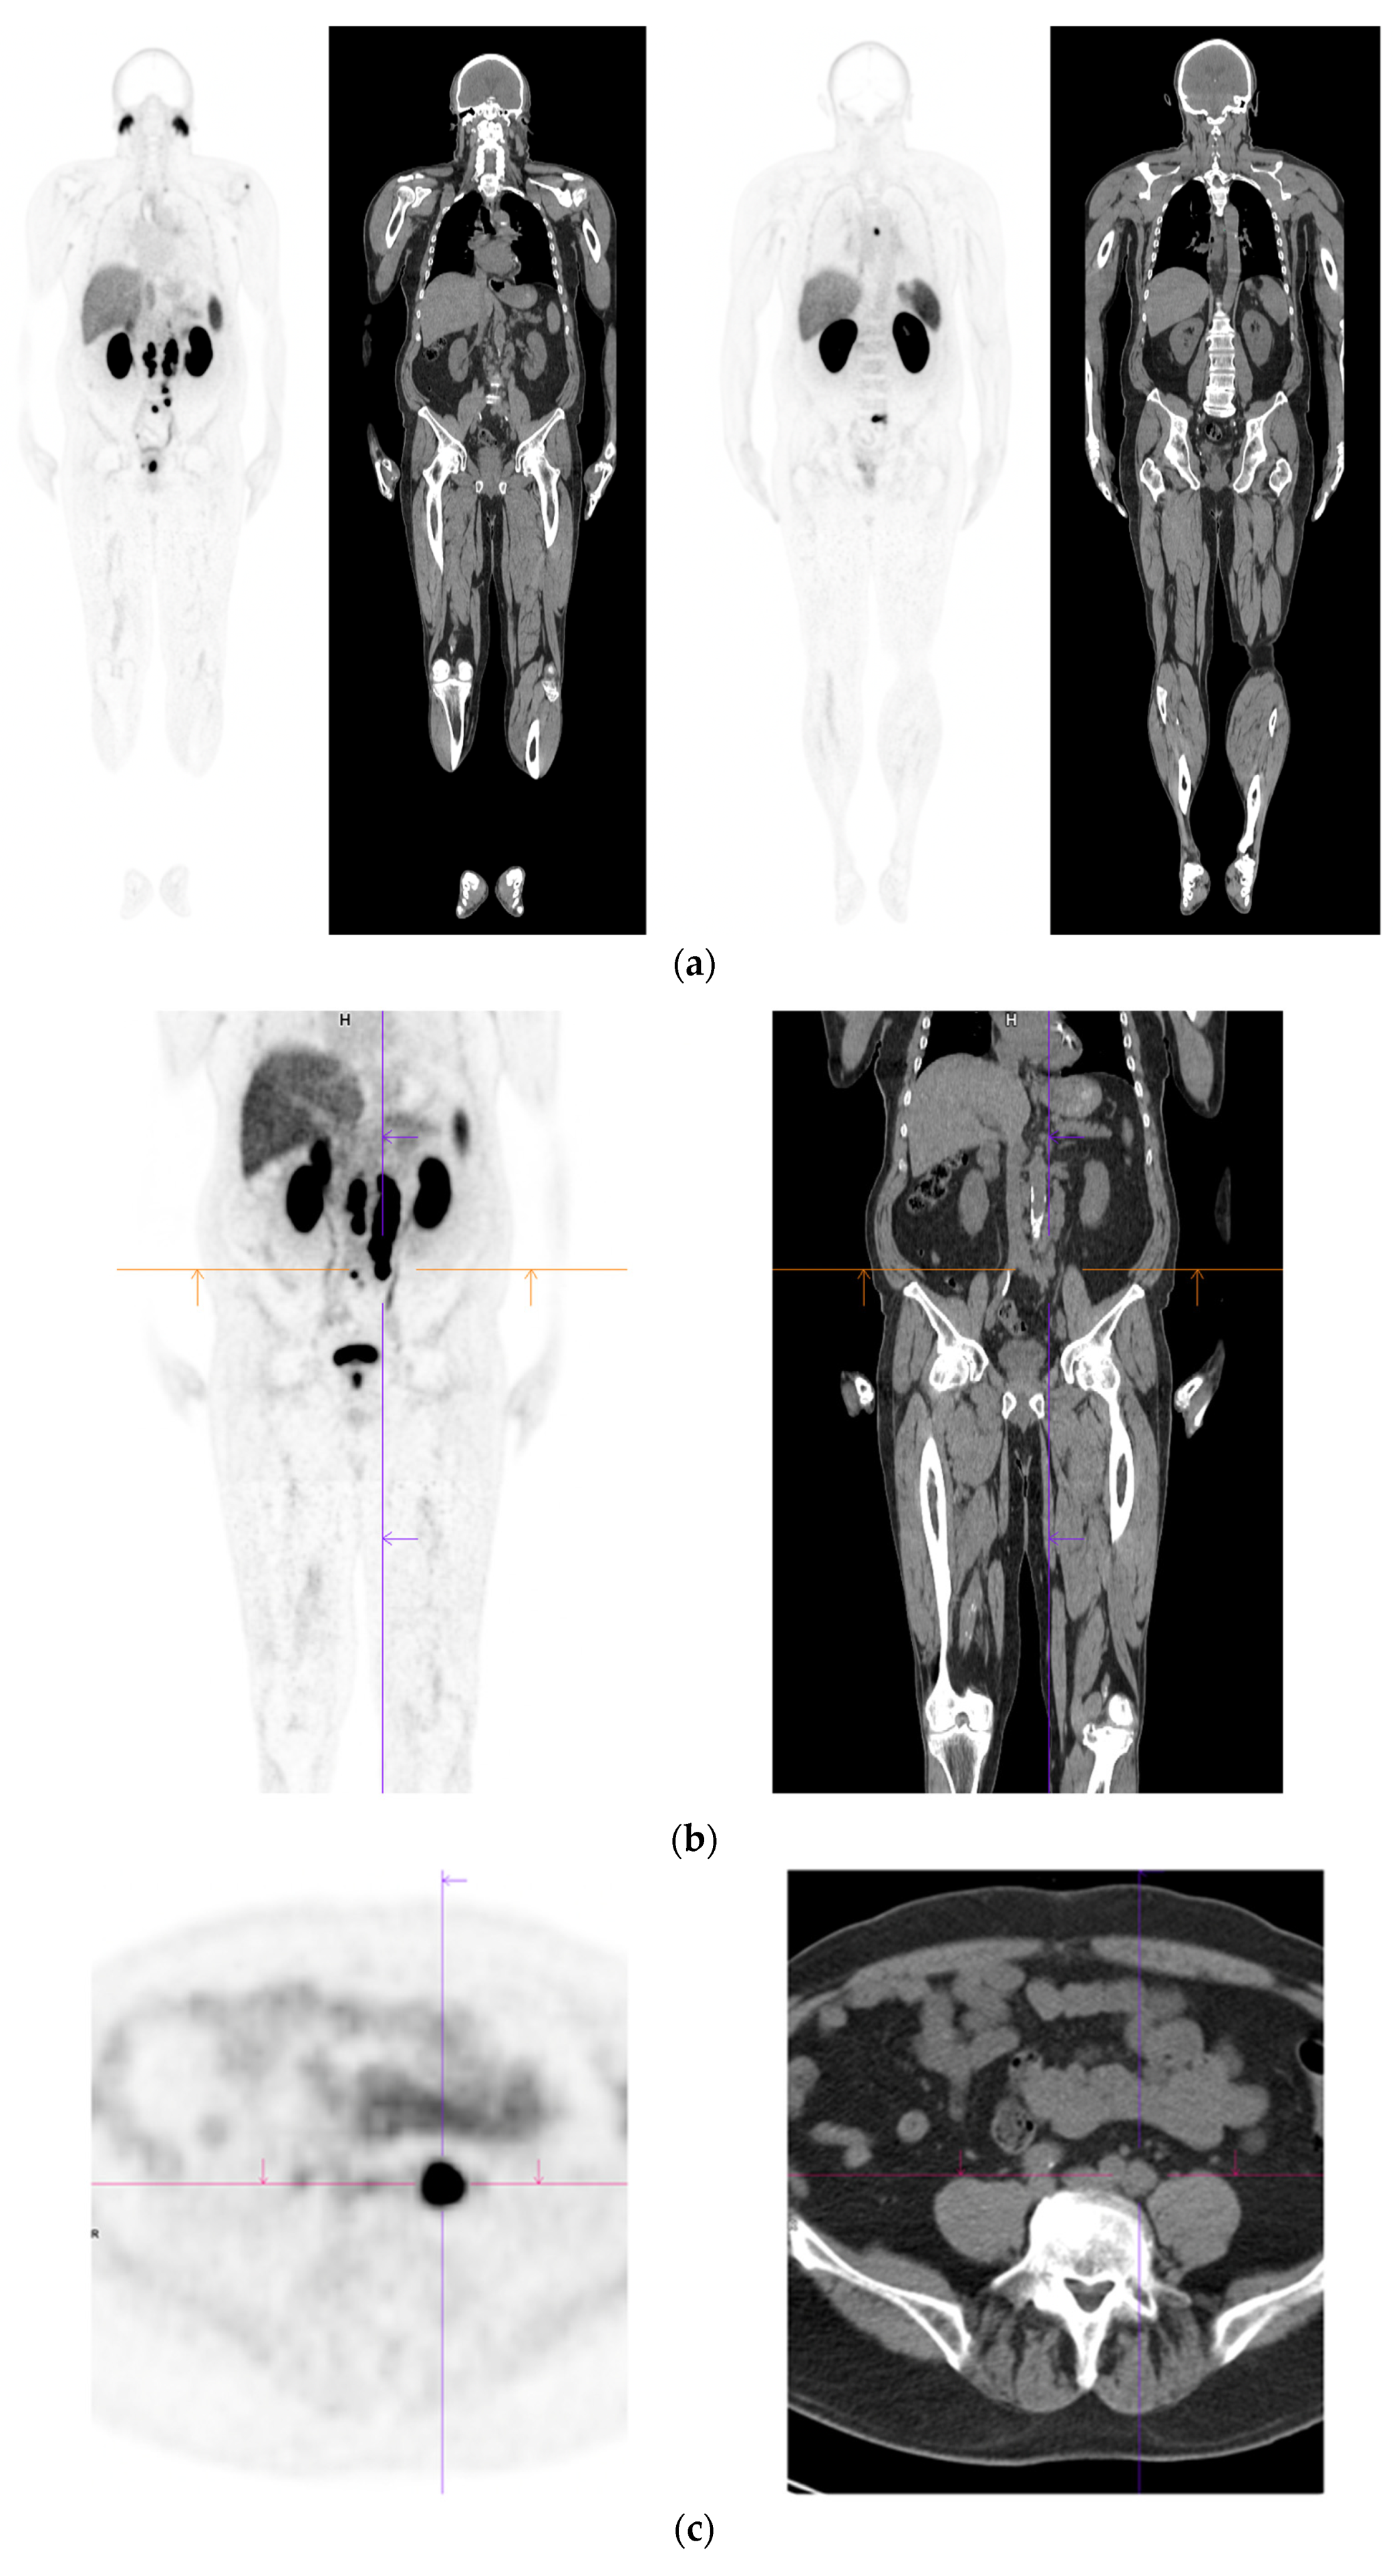

- Perera, M.; Papa, N.; Roberts, M.; Williams, M.; Udovicich, C.; Vela, I.; Christidis, D.; Bolton, D.; Hofman, M.S.; Lawrentschuk, N.; et al. Gallium-68 Prostate-specific Membrane Antigen Positron Emission Tomography in Advanced Prostate Cancer-Updated Diagnostic Utility, Sensitivity, Specificity, and Distribution of Prostate-specific Membrane Antigen-avid Lesions: A Systematic Review and Meta-analysis. Eur. Urol. 2020, 77, 403–417. [Google Scholar] [CrossRef]

- Lawal, I.O.; Lengana, T.; Popoola, G.O.; Orunmuyi, A.T.; Kgatle, M.M.; Mokoala, K.M.G.; Sathekge, M.M. Pattern of Prostate Cancer Recurrence Assessed by 68Ga-PSMA-11 PET/CT in Men Treated with Primary Local Therapy. J. Clin. Med. 2021, 10, 3883. [Google Scholar] [CrossRef]

- Barbosa, F.G.; Queiroz, M.A.; Nunes, R.F.; Viana, P.C.C.; Marin, J.F.G.; Cerri, G.G.; Buchpiguel, C.A. Revisiting Prostate Cancer Recurrence with PSMA PET: Atlas of Typical and Atypical Patterns of Spread. Radiographics 2019, 39, 186–212. [Google Scholar] [CrossRef]